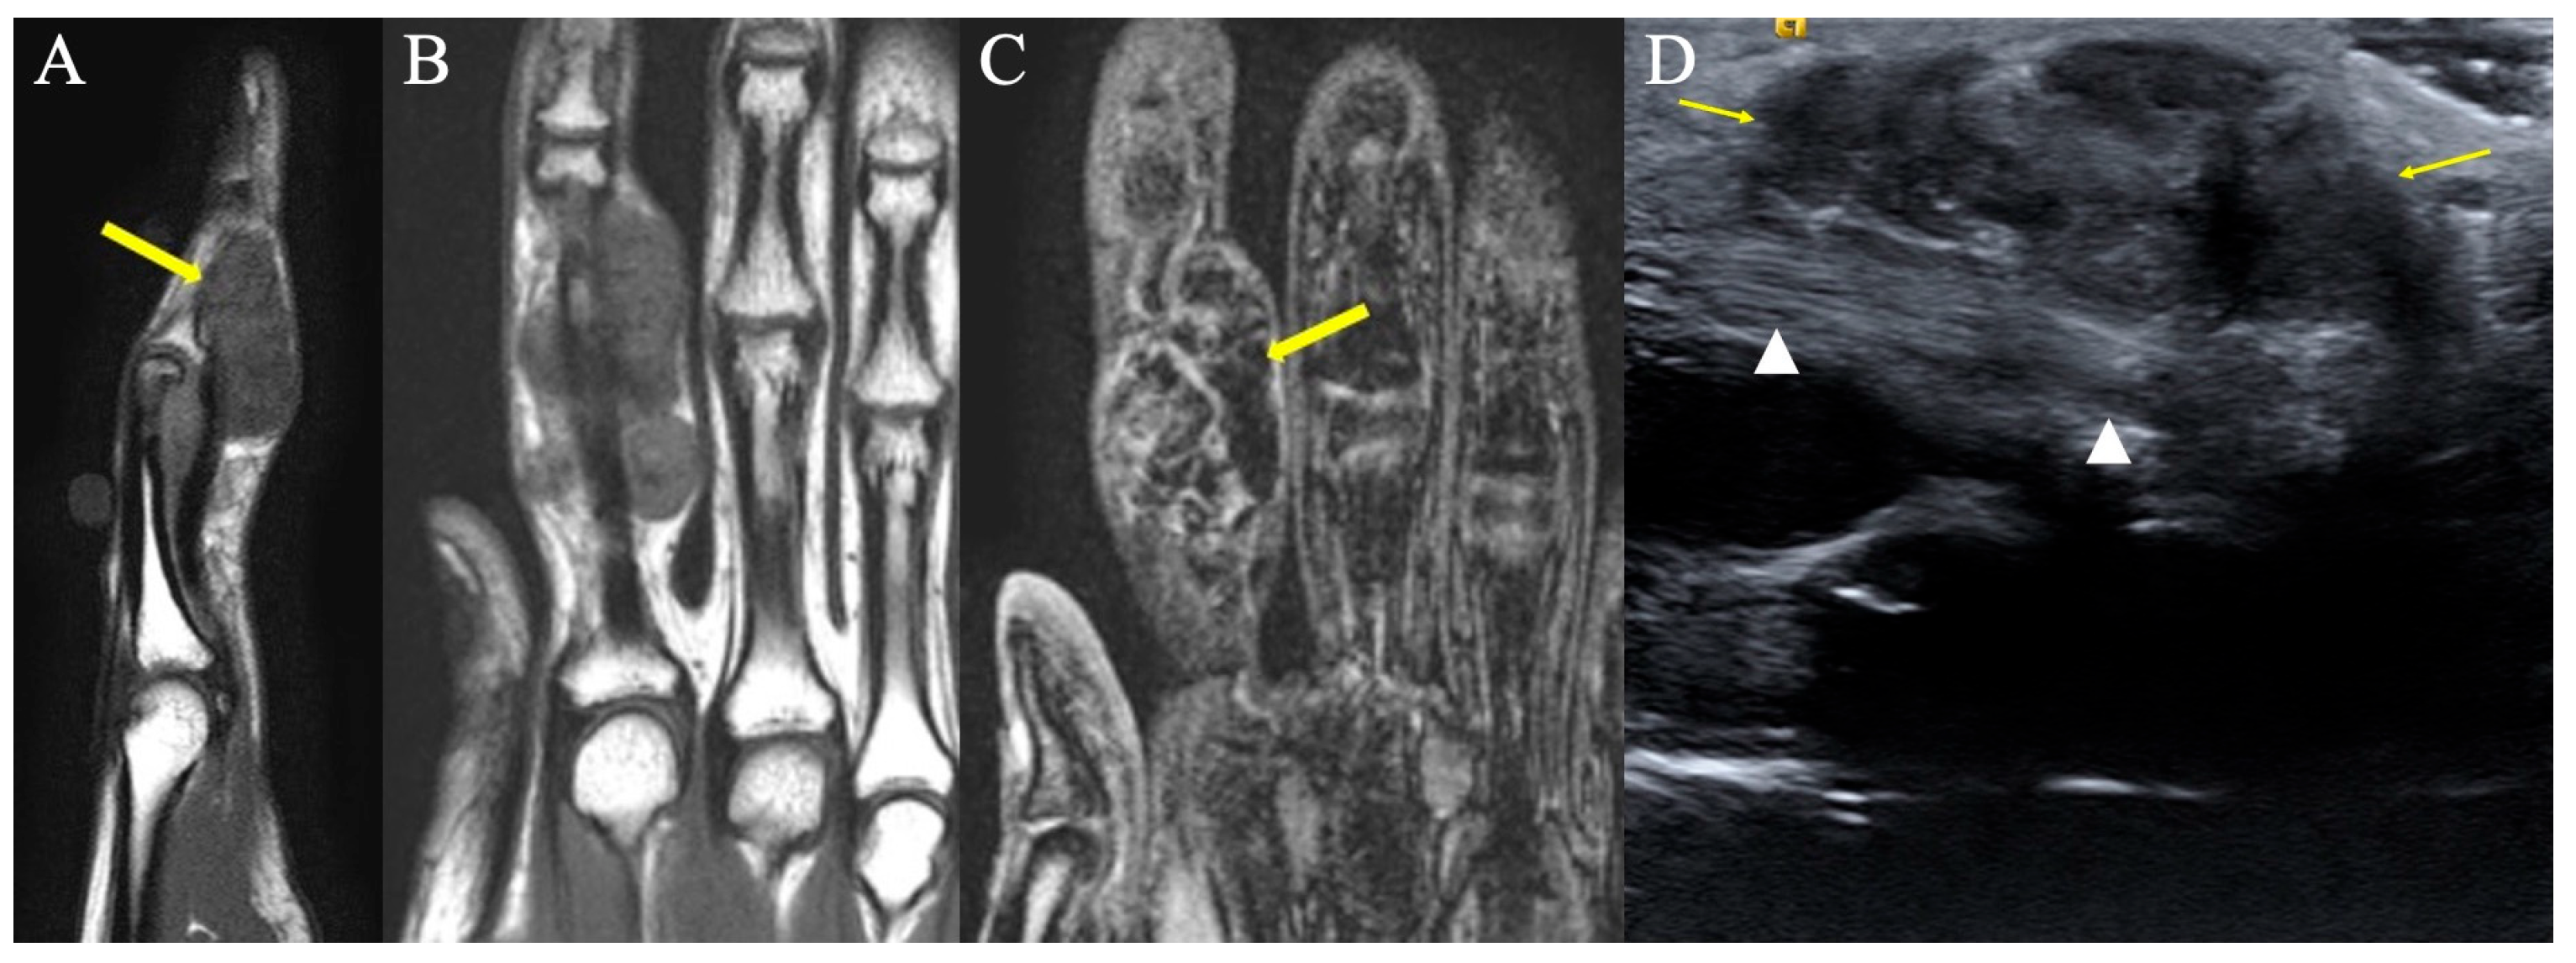

2.6. Vascular Tumors and Malformations

2.6.1. Clinical Features

2.6.2. Imaging Appearance